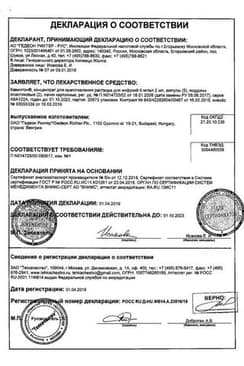

Сертификаты